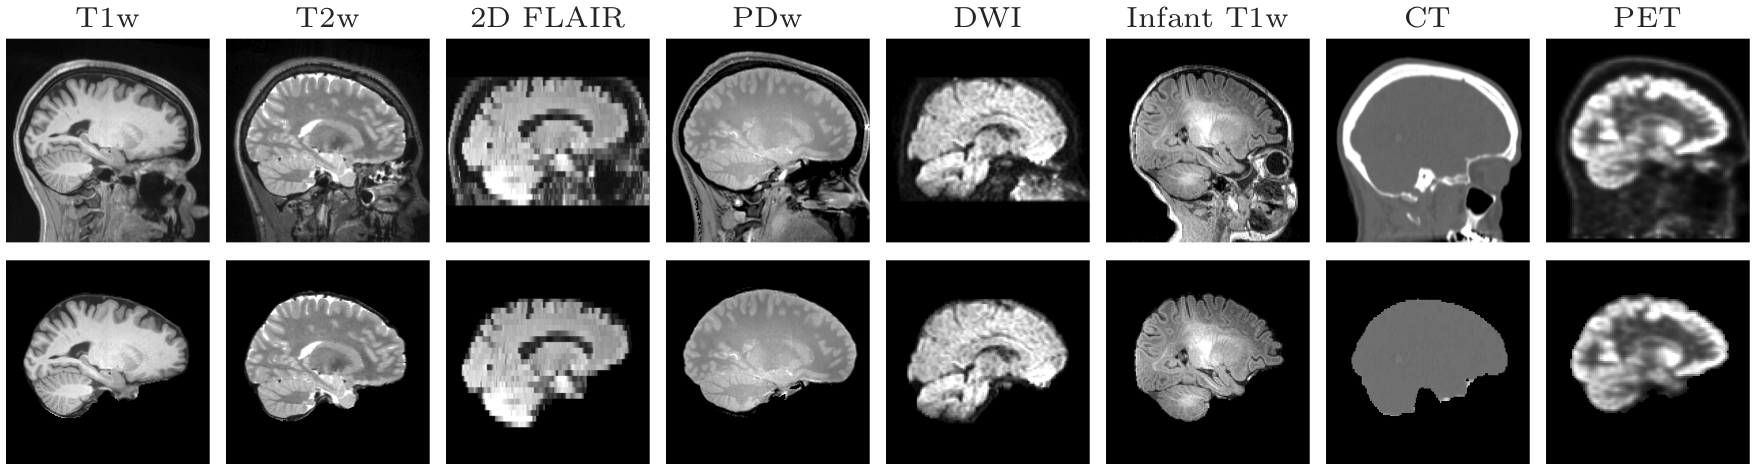

- 2022-03-24 10:45:13 435451 - AndrewHoopes ATTNEW: skullstrips.png view get